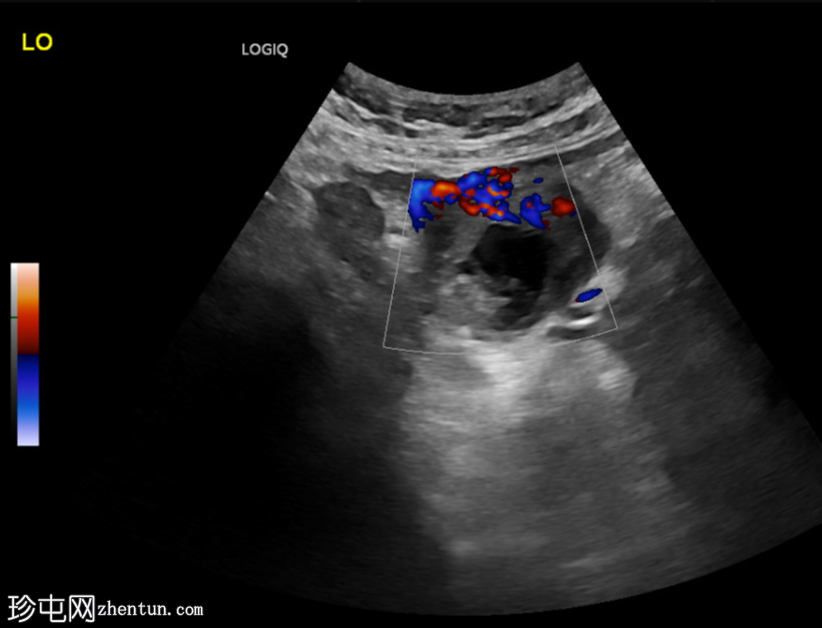

纵切面

左侧卵巢明显增大,可见一囊肿,大小约3.2 x 2.3 cm,呈火环征,可能为黄体囊肿。左侧卵巢与子宫之间可见一管状结构,直径约1.3 cm,内含浑浊液体,未见血管,最可能为输卵管积血。以上特征提示可能为左侧异位妊娠。

未见宫内妊娠囊。